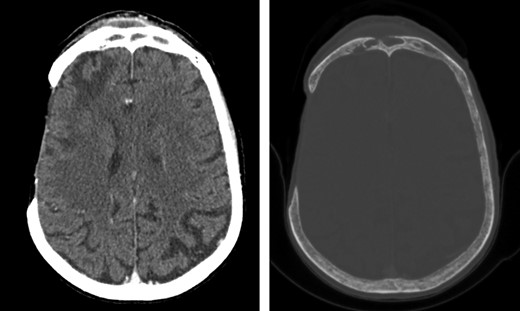

As demonstrated in Fig. 1, the computerized tomography imaging of the head revealed a right-sided subperiosteal forehead collection and a right-sided extra-axial collection with underlying frontal lobe oedema, associated with erosion of the anterior and posterior wall of the right-sided frontal sinus.

Axial computed tomography images of the head (left: brain window; right: bone window) showing a right-sided subperiosteal forehead collection and a right-sided extra-axial collection with underlying frontal lobe oedema, associated with erosion of the anterior and posterior wall of the right-sided frontal sinus. The images also show the previous right-sided temporal craniectomy defect with gliotic changes.